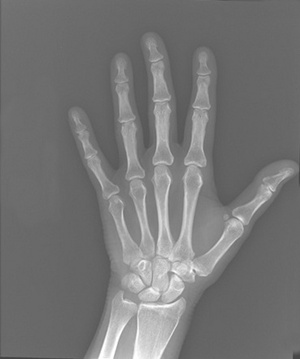

치과에서 교정 치료를 할 때에도 이런 골격적인 성장이 매우 중요하며 골격 성장의 양과 패턴에 따라 치료 방법이 결정되기도 한다. 간혹 치과에 교정치료를 위해 내원 하였을 때 얼굴 x-ray 말고도 손의 사진을 찍기도 한다. 왜 찍냐고 의아해 하시는 이들도 있겠지만 성장의 평가에 있어서는 반드시 필요한 사진이다. 손가락과 팔목을 이루는 뼈의 형태로 성장정도와 잔여 성장을 짐작할 수가 있기 때문이다.

사람의 손가락은 엄지를 제외하고는 세 개의 뼈로 이루어져 있다. 제일 끝부분을 말절골, 중간을 중절골이라고 부르며 각각의 뼈 사이에는 골단(epiphysis)이 있는데 성인에서는 각각의 뼈와 붙게되어서 보이지가 않는다. 즉 손사진만 보아도 어린이인지 성인인지 구별할 수가 있게 된다.

이중에서 엄지의 척측 종자골이 나타나게 되는 시기는 키가 가장 많이 자라는 최대 성장기의 약 1년전 쯤에 관찰 되므로 매우 중요한 포인트가 된다. 잔여 성장을 예측할 때 중요한 손가락뼈는 중지와 약지이다. 또한 손목의 요골의 융합정도를 가지고 성장 완료 시기를 확인할 수 있는데 중간부터 붙어서 서서히 가장자리까지 붙으며 가장자리 끝만 조금 남기고 융합이 되었다면 거의 성장 종료시기라고 해석할 수 있고 더 이상 키는 크지 않는다고 할 수 있다.

치과에서 교정치료를 할 때에도 이런 손의 뼈들을 참고해서 헤드기어나 고정식 교정장치, 발치등의 결정을 하게 되고 주걱턱이나 무턱 때문에 양악수술을 할 때에도 손목사진을 참고로 수술시기를 결정하게 되므로 매우 중요한 사진이라고 할 수 있겠다. 강남구 대치동 선릉역 뉴연세치과 우용제 원장(사진)은 "손목 사진은 교정치료를 위해 매우 중요한 사진이며 필요하다면 언제 시작해야 하는지, 교정치료가 필요한지를 판단하는 중요한 요인이기 때문에 가까운 교정 전문 치과를 찾으셔서 치료를 위한 적절한 시기를 찾는 것이 무엇보다 중요하다"고 밝혔다. /생활경제팀 osenlife@osen.co.kr